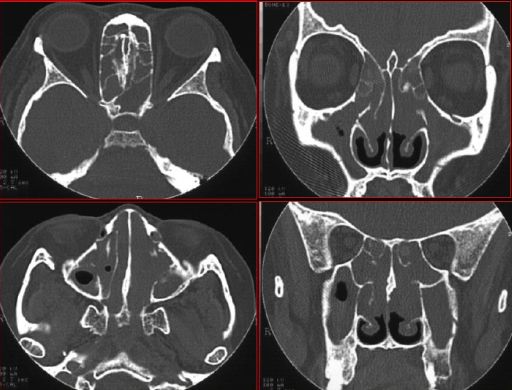

急性鼻窦炎

筛窦异物伴急性感染